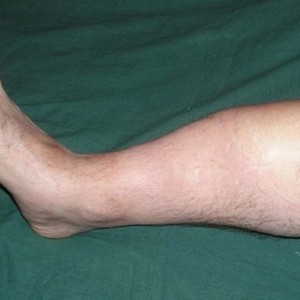

Ложные суставы и несросшиеся переломы тесно связаны между собой, так как суставные сочленения формируются в местах нарушения целостности костей. В связи с этим, основная жалоба пациента – появление необычной подвижности в области конечности, например, в середине голени. Важно отметить, что если сегмент конечности состоит из двух костей (предплечье, сформированное лучевой и локтевой костью), а суставное сочленение сформировалось на одной из них, то подвижность может отсутствовать.

При надавливании на область патологического движения пациент может ощущать слабый болевой синдром, или же вовсе не чувствовать каких-либо неприятных ощущений. Боль возникает в тех случаях, когда конечность подвергается сильной нагрузке.

При формировании врожденного ложного сустава, у ребенка отмечается выраженная подвижность ноги или руки в необычном месте. Очень часто, патология выявляется в том момент, когда малыш начинает активно ползать, ходить или брать предметы в руки.